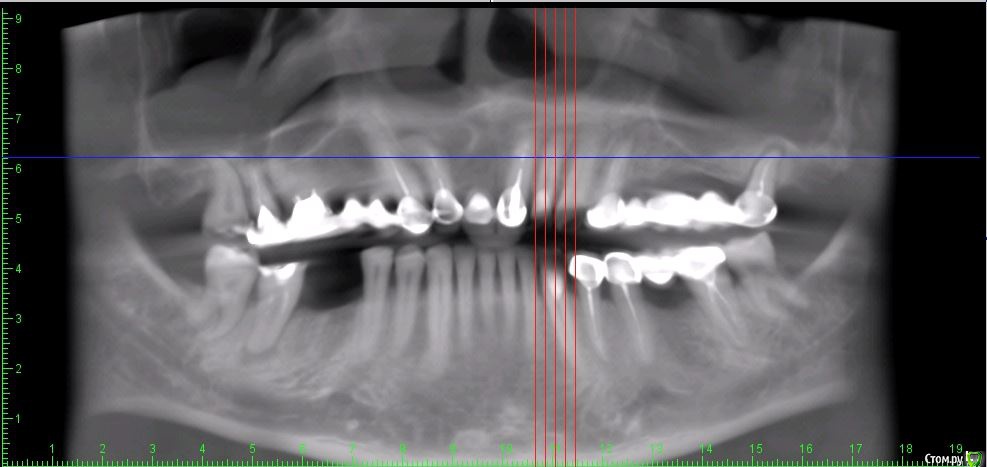

Дмитрий Л. Опубликовано 16 ноября, 2018 Поделиться Опубликовано 16 ноября, 2018 (изменено) Здравствуйте всем)Ситуация такая: старый мост 24-28. 28 симптоматичен, пациент принимает аб и противовосп. Имеется: - 24 перирадикулярные изменения (асимптомно)- 28 перирадикулярные изменения (обострение)- утолщение слизистой гайморовой (асимптомно)- невозможность имплантации в обл 26 (высота кости не позволяет) Пожелания пациента:- удаление 28 - желание сохранить мост - имплантация - нежелание носить съемную конструкцию Как планирую я:- перелечить 24, кальций 2-6 мес.- удалить 28- изготовить съёмник- выждать 4-6 мес. Повторить КТ, оценить гайморовую- имплантация 25, имплантация "где-то в обл 27" - всеми силами избежать синуса Мои грёзы:1. Ставить вблизи 24 - риск. Нужно лечить 24... реэндо... долго... может удалить? 2. Я верю, что причина хр гайморита - 28. Так ли это? Стоит ли ожидать позитивной динамики? 3. На сколько уйдёт кость после удаления 28 за 4-6 мес.? Её и так мало... Станет ли меньше? Графтить 28 не хочу. Там микробы. 4. Объём кости в обл 27-28 требует коротышку. Первыми приходят на ум Штрауман 6 мм (4 мм в кости, станет красиво) или ЭниРидж (бикортакально, скорее всего в пазуху на 1-2 мм). Нюанс в том, что я не работал этими системами... И коротышки не ставил. В общем придётся искать наборы, но это мои проблемы. 5. Итоговая конструкция: мост 25-27. При чём 27 имеет длину 4-6 мм, не слишком ли короткая дистальная опора? Вот спланировал приблизительно так... Надеюсь на отклик. Изменено 16 ноября, 2018 пользователем Дмитрий Л. Ссылка на комментарий

Irouil Опубликовано 16 ноября, 2018 Поделиться Опубликовано 16 ноября, 2018 (изменено) Без синуса это 2.5-2.8? Мне кажется надо синусить и нормально имплантировать, только с носом разобраться предварительно Апдейт: перечитал тс, 2.5-2.7. я бы, перед тем как стучать, сделал КТ соустья. Изменено 16 ноября, 2018 пользователем Irouil 1 Ссылка на комментарий

колесников Опубликовано 17 ноября, 2018 Поделиться Опубликовано 17 ноября, 2018 Не пойму о чем речь. 24 удаляется. Прекрасно проходят 24,25,27 без синусов (ну может 1 витком у 27го за дно бы зацепился,но это не точно. Когда у пациента случится обострение в пазухе,он пойдёт к ЛОРу ,а тот скажет -всему виной стоматологи,удаляйте Имплант, даже клкт «до» не помогает разъяснить происходящее,пациент остаётся с сомнением,ведь Доктор так сказал! А стоматолог как известно не врач,его слушаем в пол уха. Не советую в такую пазуху заходить.На 27 широкий формирователь,24,25 с нагрузкой. Возможно сст у 24,смотря как удаление пойдёт, 25 раскрыть роллом. Будет и красиво и быстро и функционально 2 Ссылка на комментарий